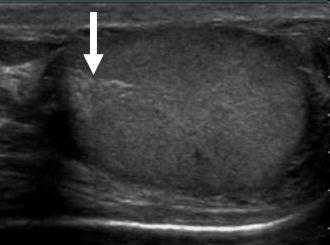

Как мы знаем, белочная оболочка по задней поверхности вдается в паренхиму яичка и формирует перегородку, которую можно увидеть при УЗИ. Перегородка яичка визуализируется в продольной плоскости яичка как эхогенная линейная полоска. Также во время исследования доктор может увидеть следующие структуры: сеть яичка, головку, тело и хвост придатка. Образовавшиеся в яичках сперматозоиды через сеть яичка попадают в выносящие канальцы, которые формируют головку придатка яичка. Сеть яичка выглядит как гипоэхогенная или разделенная перегородками кистозная область около головки придатка. Головка придатка на УЗИ визуализируется как образование треугольной формы с закругленными краями такой же эхогенности, что и яичко. Также в процессе обследования должны визуализироваться тело и хвост придатка. Однако хвост придатка очень маленький и локализуется кзади, что не всегда позволяет увидеть его при УЗИ.

На данном изображении яичка в продольной плоскости визуализируется перегородка яичка в виде эхогенного образования.

На ультразвуковом изображении в продольной плоскости визуализируется сеть яичка в виде гипоэхогенной области разделенной перегородками.